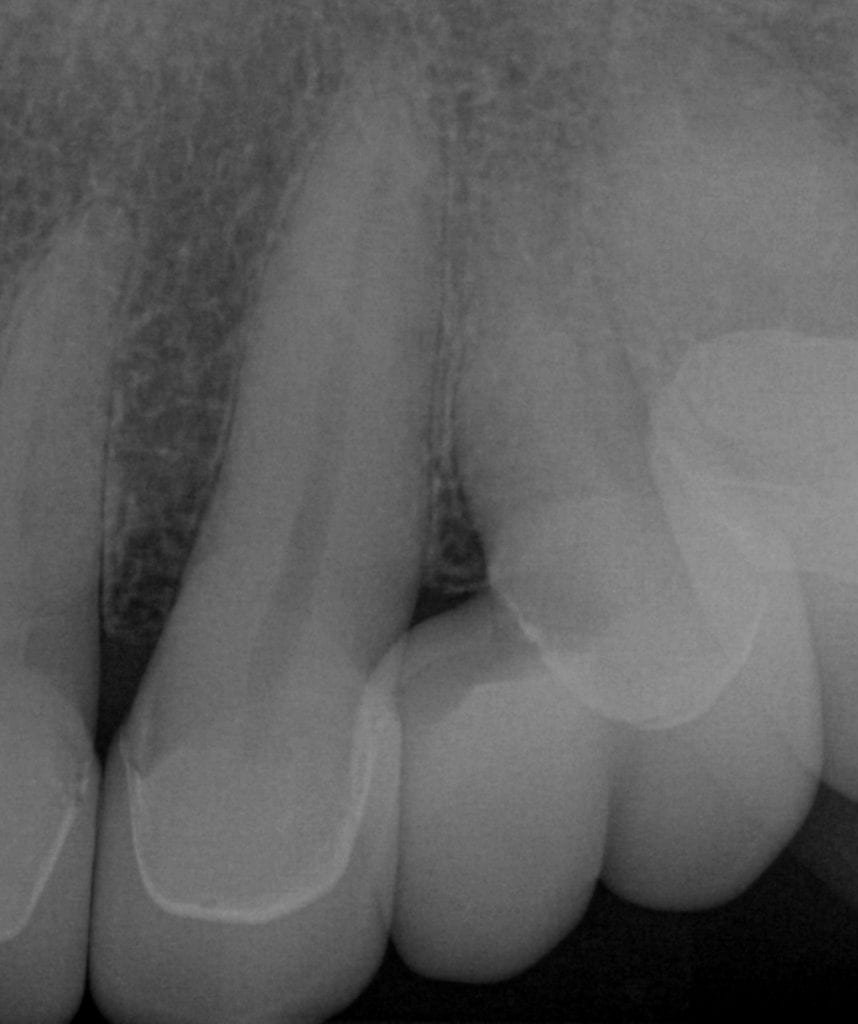

ONE WEEK POST-OP RADIOGRAPHS / CEMENT CHECK